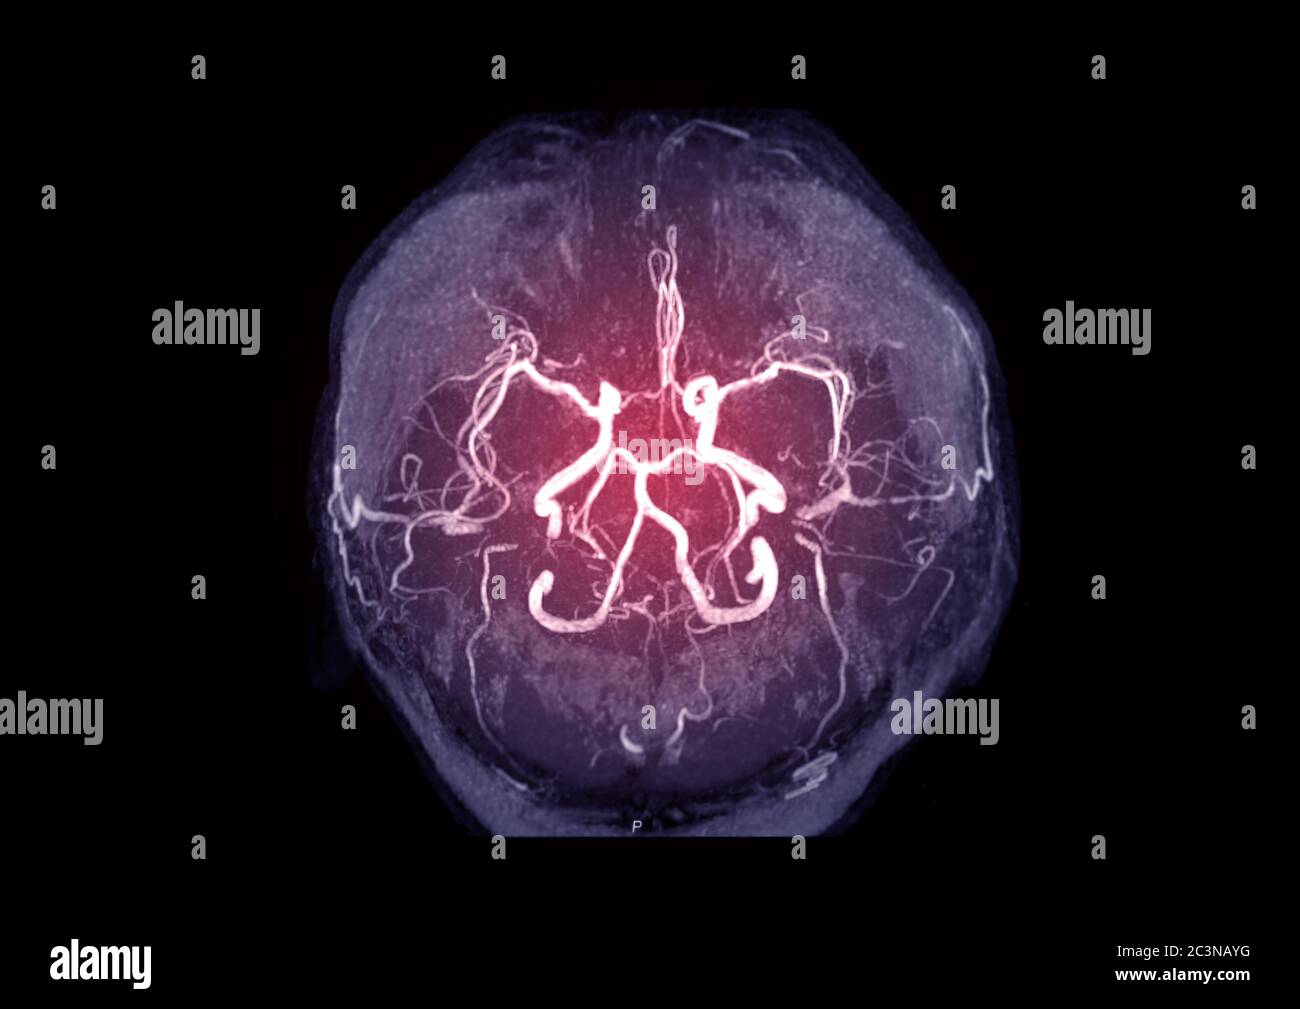

Plaque In Arteries Of The Brain . Atherosclerosis is a condition characterized by the buildup of fatty deposits, or plaques, on the inner walls of arteries. Intracranial stenosis, also known as intracranial artery stenosis, is the narrowing of an artery in the brain, which can lead to a stroke. The narrowing is caused by a buildup and hardening of fatty. Carotid artery disease occurs when fatty deposits, called plaques, clog the blood vessels that deliver blood to the brain and head (carotid arteries). Intracranial atherosclerosis is the build up of a sticky substance called plaque in the arteries that supply the brain with blood, causing the narrowing and blockage of these vessels. Here we provide an overview of the. Plaque can cause an artery to become narrowed or blocked. Intracranial large and small arterial calcifications are a common incidental finding on computed tomography imaging in the general population. If there's too much cholesterol in the blood, the cholesterol and other substances may form deposits called plaque. White matter disease is an umbrella term for damage to your brain’s white matter caused by reduced blood flow to the tissue.

Carotid artery disease occurs when fatty deposits, called plaques, clog the blood vessels that deliver blood to the brain and head (carotid arteries). Intracranial large and small arterial calcifications are a common incidental finding on computed tomography imaging in the general population. The narrowing is caused by a buildup and hardening of fatty. Intracranial stenosis, also known as intracranial artery stenosis, is the narrowing of an artery in the brain, which can lead to a stroke. Plaque can cause an artery to become narrowed or blocked. White matter disease is an umbrella term for damage to your brain’s white matter caused by reduced blood flow to the tissue. Atherosclerosis is a condition characterized by the buildup of fatty deposits, or plaques, on the inner walls of arteries. Here we provide an overview of the. Intracranial atherosclerosis is the build up of a sticky substance called plaque in the arteries that supply the brain with blood, causing the narrowing and blockage of these vessels. If there's too much cholesterol in the blood, the cholesterol and other substances may form deposits called plaque.